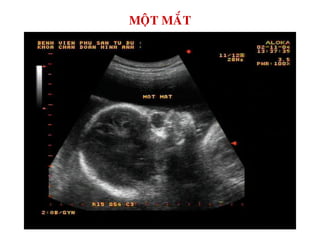

MOÄT MAÉT